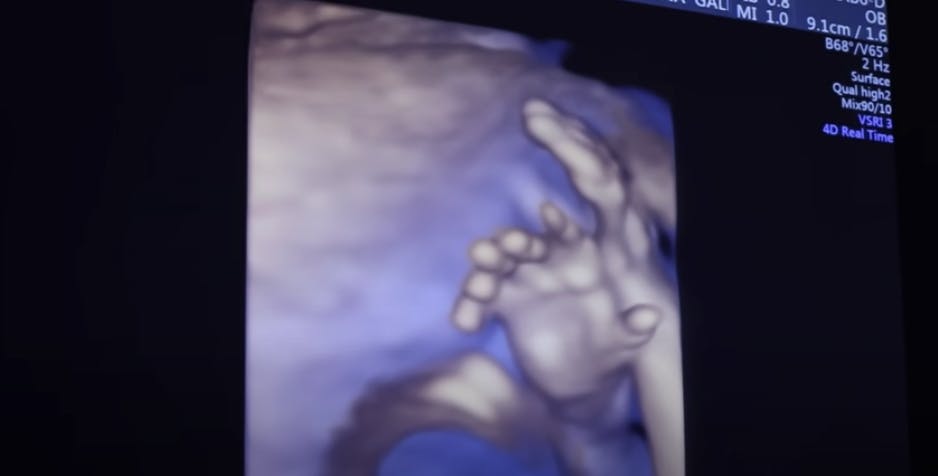

Scanningen viser, at pigen, der vokser i hendes mave, har seks fingre på hver hånd. Det vil sige, at barnet har i alt 12 fingre.

Her vinker seks fingre ud til far og mor. Foto: YouTube / Tammy Hembrow